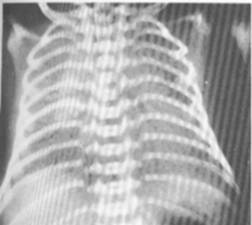

Fig. 103 - Forma medie cu opacitati reticulo-granulare bilateral

Fig. 104 - Forma severa cu aerare diminuata si bronhograma aerica.

- in cazurile severe, radiologic se evidentiaza o aerare aproape absenta a plamanilor si prezenta de aer in bronhii (‘’ bronhograma aerica’’);

- in formele medii se observa opacitati reticulo-granulare in ambii plamani, datorate suprapunerii nodulilor acinari (cauzati de alveolele atelectaziate) si a bronhiilor dilatate.